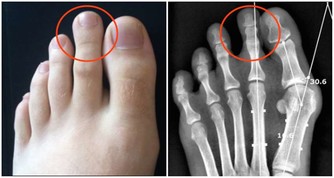

老年人由於身體各方面機能下降,運動要以自身能接受為宜,可適當進行快走等運動方式,避免長時間爬樓、爬山等,以免損傷膝關節。